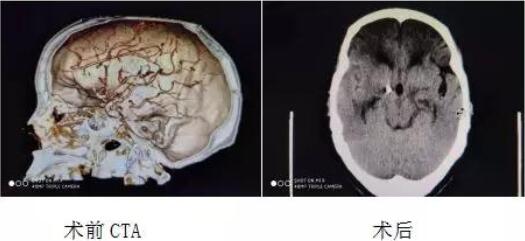

男同视频 成功开展颅内动脉瘤夹闭术及脑血管造影动脉瘤栓塞术